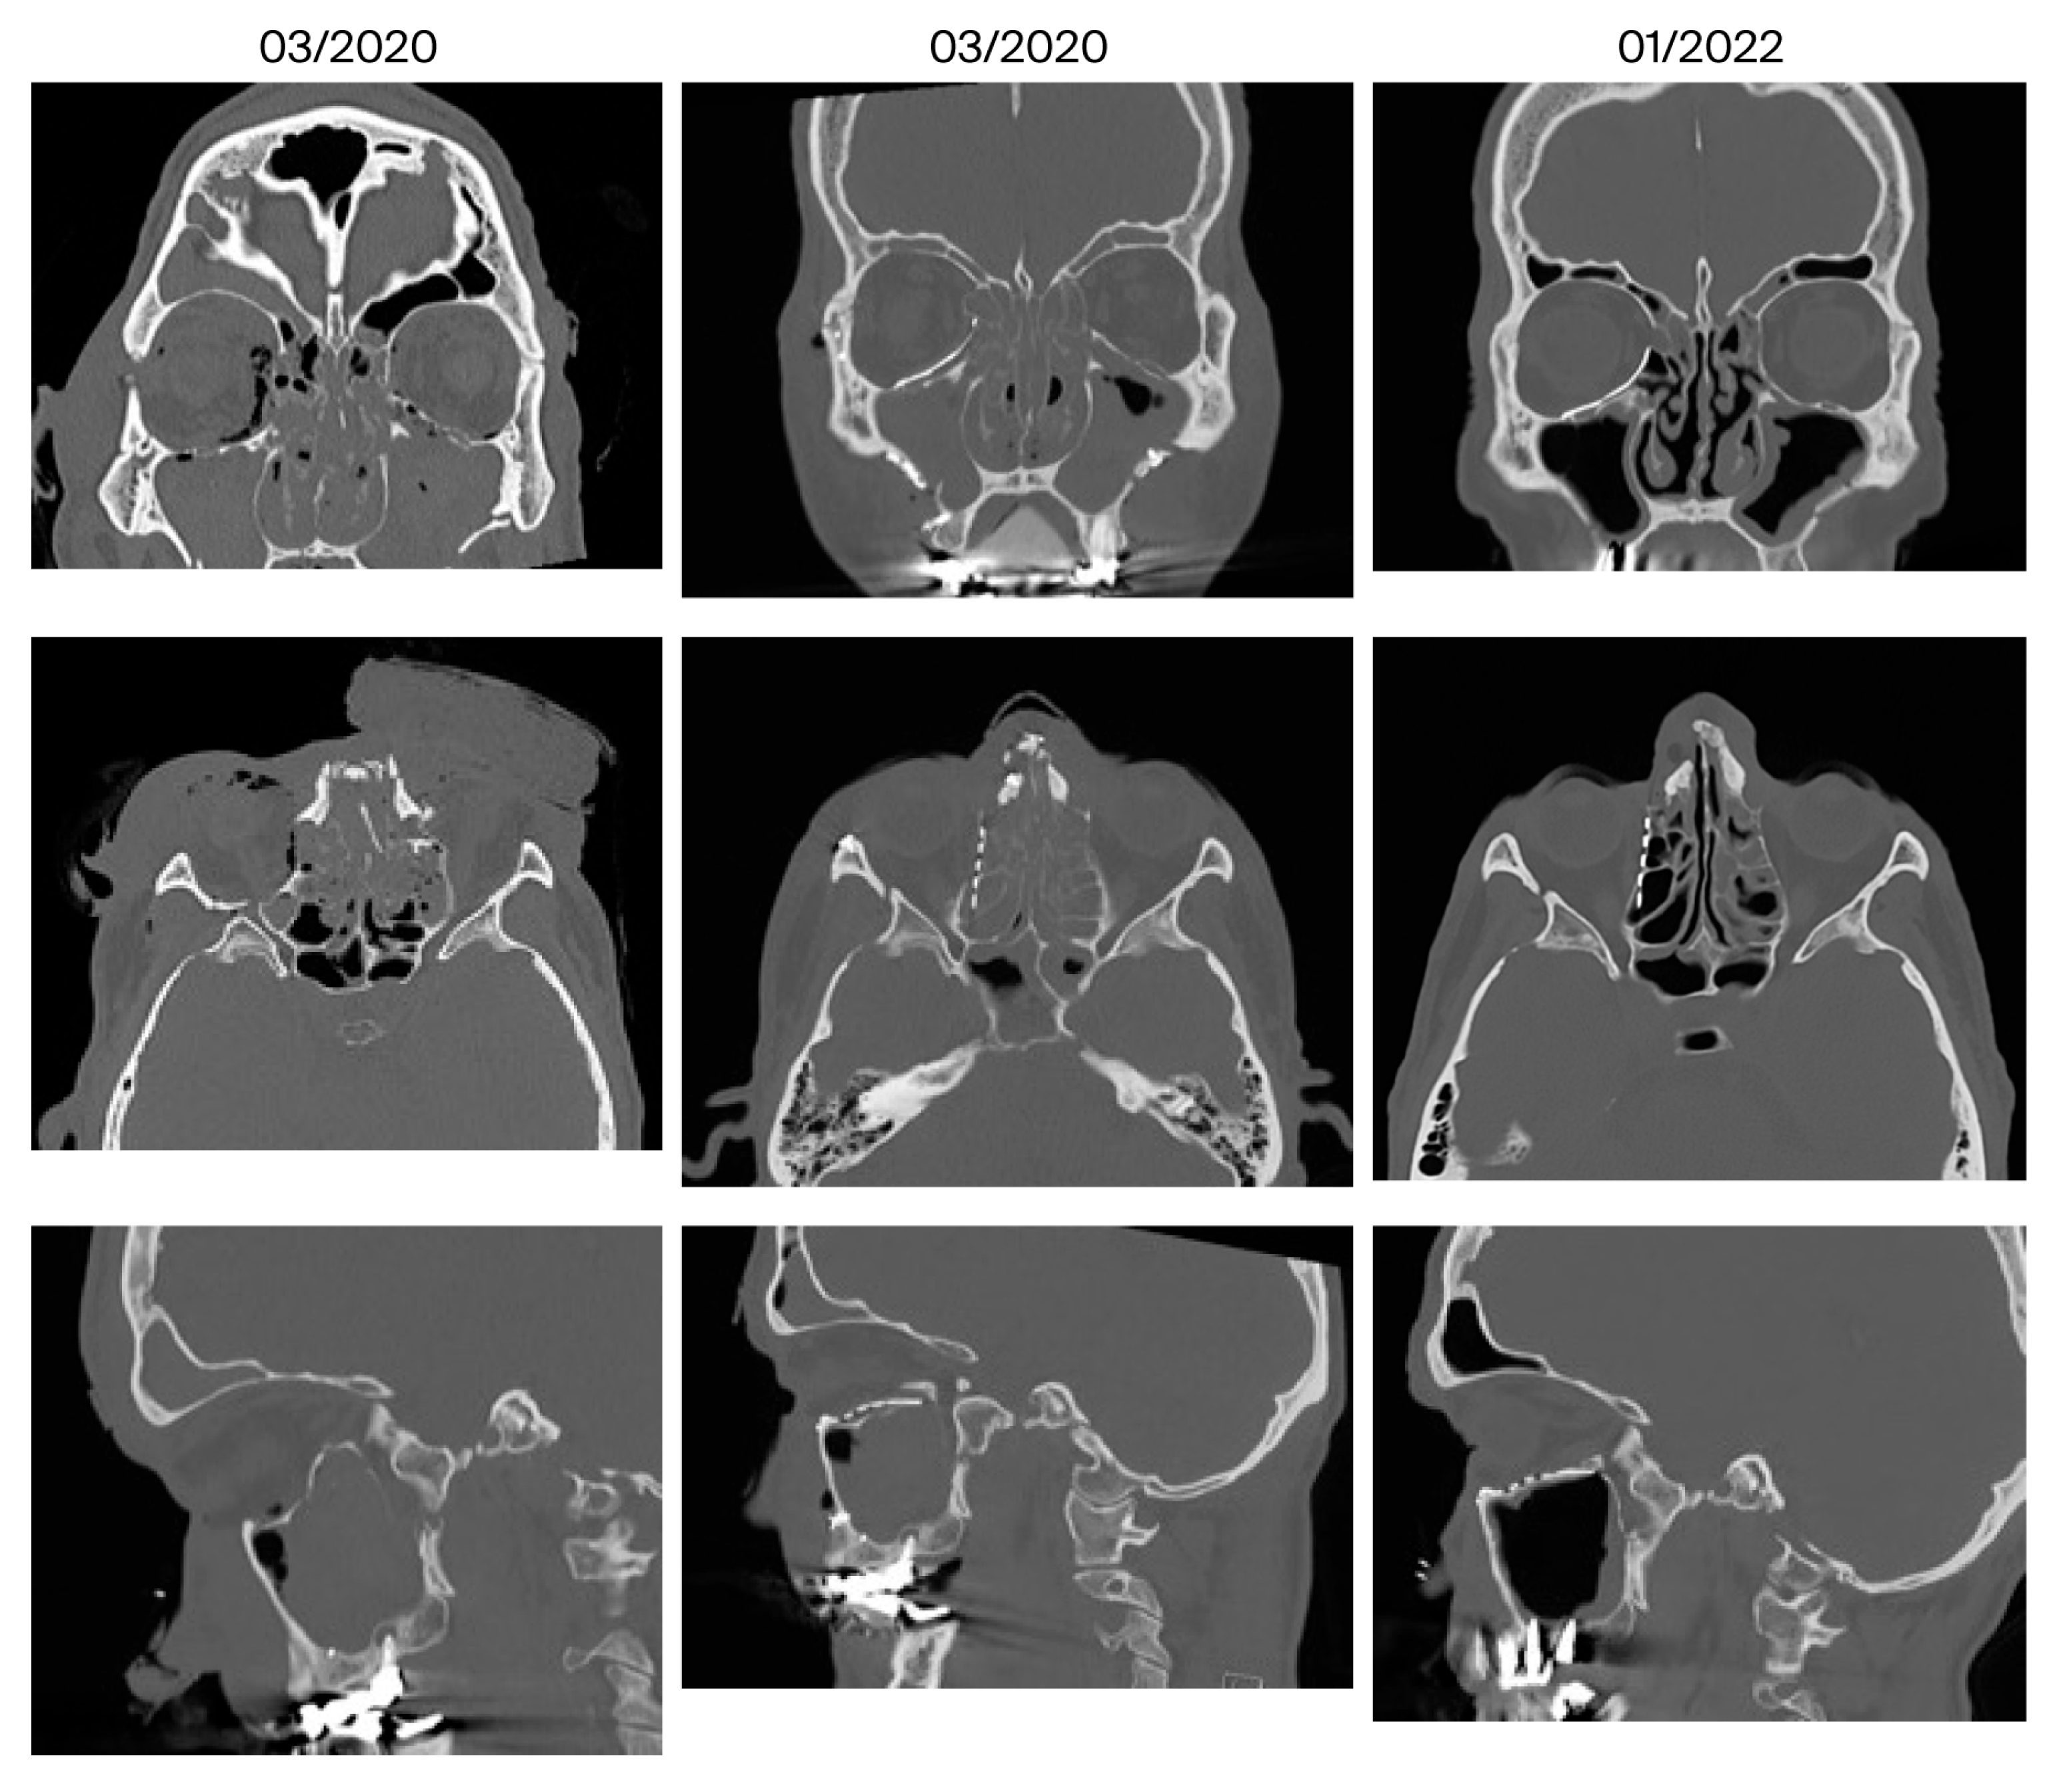

- Bone apposition at the PSI as a sign of osseointegration (n = 16)

- Remodeling of the dislocated bone fragments of the orbital walls (n = 16), including in the area of the infraorbital canal.

| 10 | March 2020 January 2022 (22 months) | Anosmia, migraine | Mucosal swelling | 3/5 | No | Ethmoidal | Yes |

| 11 | December 2023 February 2025 (14 months) | Infraorbital hypesthesia | No | 6/3 | Yes | No | Yes |